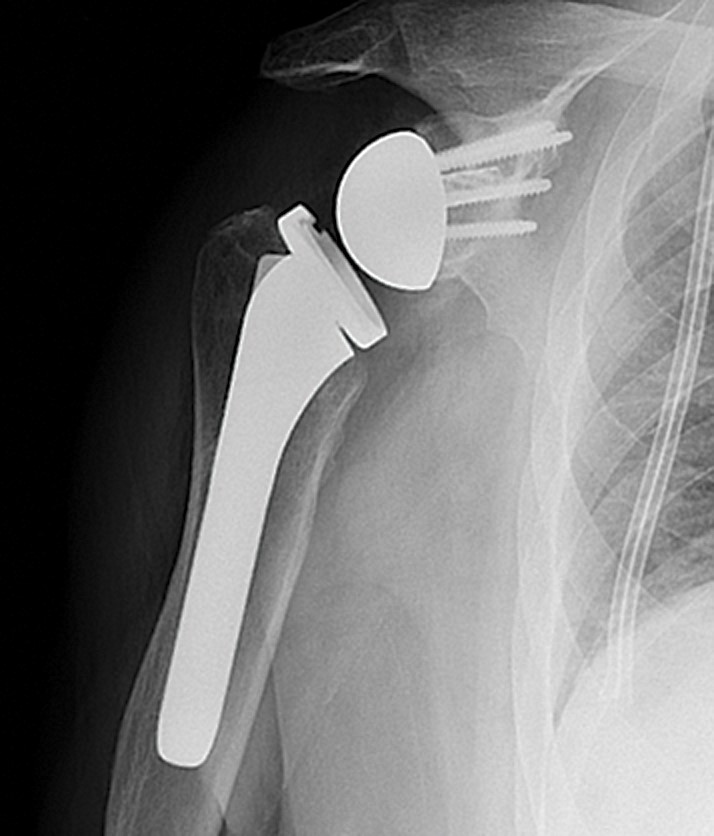

تعویض مفصل شانه Shoulder Joint Replacement

کاندید های اصلی تعویض کامل مفصل شانه، افراد مبتلا به بیماری های آرتریت روماتوئید و استئوآرتریت می باشند. در این روش درمان در صورتی که آناتومی مفصل در طی درمان حفظ شود، نتیجه موفقیت آمیز خواهد بود. همی آرتروپلاستی یا تعویض سطح مفصلی استخوان هومروس معمولاً در شکستگی های خرد شونده ی سر و گردن هومروس و یا در مراحل ثانویۀ درمان شکستگی های بد جوش خورده یا جوش نخورده کاربرد دارد.